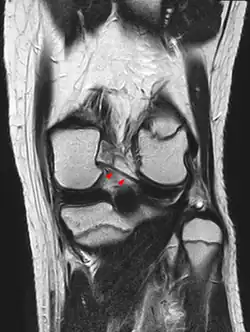

Posterior meniscofemoral ligament on MRI, coronal -